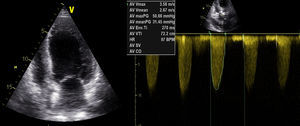

O ecocardiograma transtorácico (Figura 1) mostrou ventrículo esquerdo não dilatado, com ligeira hipertrofia do septo interventricular, com boa função sistólica global (FSG) e segmentar; válvula aórtica fibrocalcificada com gradiente transvalvular máximo de 74 e médio de 49mmHg e área calculada por equação de continuidade de 0,77cm2.

O doente teve alta ao 24.° dia de internamento, em classe NYHA II. No ecocardiograma transtorácico à data de alta apresentava compromisso moderado a grave da FSG (Figura 4), gradiente valvular aórtico médio de 31mmHg e área valvular de 1,06cm2. Programou-se cirurgia cardíaca, após cumprimento de um mês de dupla antiagregação plaquetar.

A suspensão de noradrenalina foi realizada em menos de 24h. Contudo, o doente manteve quadro de ICA, dificultando o processo de extubação, com várias tentativas sem sucesso. Ao oitavo dia de internamento, foi decidida terapêutica com levosimendan em perfusão (sem dose de carga, dose de manutenção de 0,1mcg/kg/min), que decorreu sem intercorrências. Houve melhoria clínica significativa, com extubação cerca de 24h depois. O ecocardiograma evidenciou melhoria da função ventricular esquerda (fração de ejeção de 40%), com gradiente valvular aórtico médio de 47mmHg.